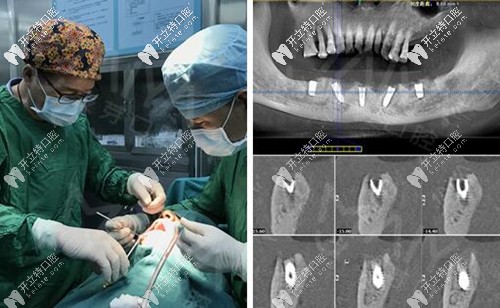

麥芽口腔的種植牙博士看過(guò)我的片子后,說(shuō)我的下半口牙槽骨萎縮厲害,現(xiàn)存的骨量不適合做傳統(tǒng)的滿口種植牙手術(shù),因此給我設(shè)計(jì)了“all-on-4”種牙技術(shù)的升級(jí)版本“all-on-5”,也就是說(shuō)恢復(fù)半口牙齒需要種5顆植體,安裝上“架橋式”的牙冠就可以了。

其實(shí),做種植牙根本沒有自己想象的疼,打完麻藥不到5分鐘就起作用了,半口種植牙的5顆牙釘不到一個(gè)小時(shí)就種完了,感覺自己就瞇了一會(huì)就好了。牙釘種好之后,戴的是臨時(shí)牙冠,不過(guò)當(dāng)天就能吃東西~~